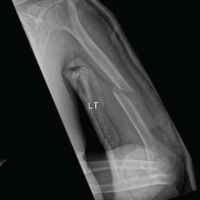

Case Report: We report the case of a 20-year-old female who presented 3 years after a conservatively treated distal radius fracture. Her complaints included wrist deformity, reduced grip strength, and intermittent pain. Imaging revealed a distal radius malunion with dorsal tilt and radial shortening, resulting in a positive ulnar variance of +4 mm, while the distal radioulnar joint (DRUJ) remained congruent. Surgical intervention involved an USO, during which a 1 cm wedge of bone was resected. At 1-year follow-up, she demonstrated excellent range of motion, full grip strength, no pain, and was highly satisfied with the cosmetic outcome.